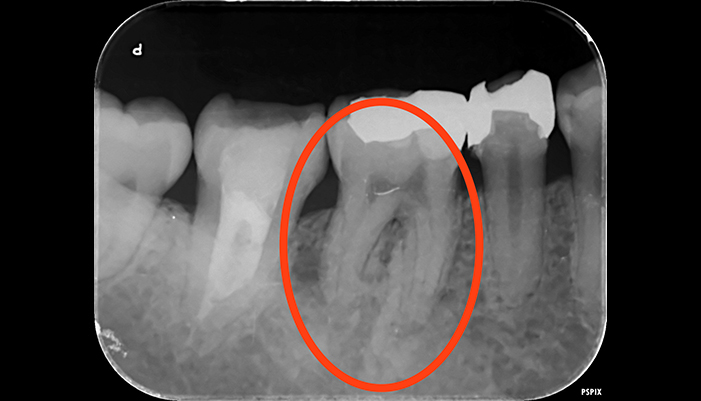

治療前

治療後

| 主訴 | 虫歯を治したい |

|---|---|

| 治療期間 | 1回 |

| 費用 | 再根管治療132,000円(税込)+ ファイバーコア44,000円(税込)= 176,000円(税込) |

| 治療内容 |

ラバーダムを用いて無菌的な環境下で再治療(過去に根管治療をしている歯の治療)を行いました。 過去に詰めた修復物の周りが虫歯になってしまっていたため、マイクロスコープ下で虫歯を完全に取り切り、 NiTiファイルを用いた根管形成、薬液や超音波器具による洗浄、体に馴染みの良い材質による充填、被せ物を支え、再感染しないように土台を立てました。 |